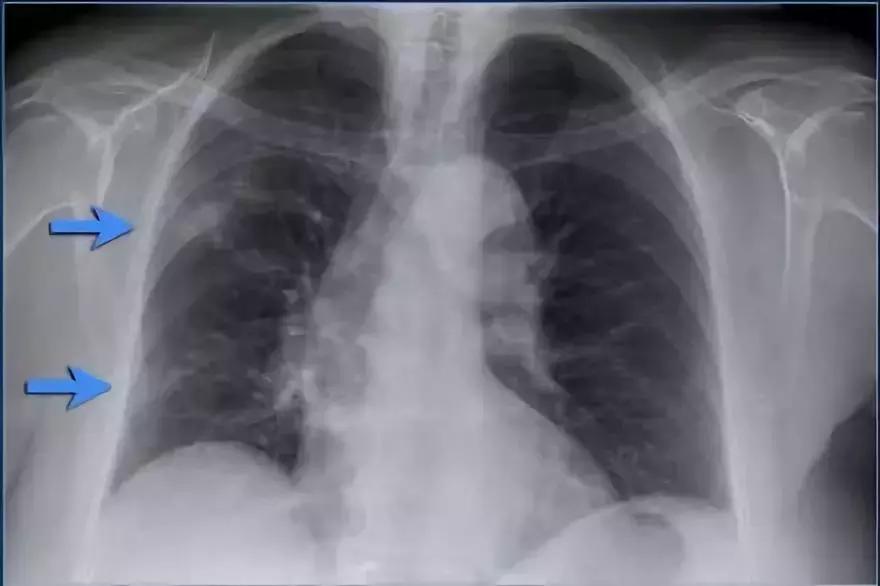

支气管肺炎弥漫性实变

➢ 患者患有高烧咳嗽,诊断为弥漫性支气管炎。

➢ 与始于肺泡的大叶性肺炎不同,支气管肺炎作为急性支气管炎始于气道。

➢ 多发模糊阴影,进展期能产生弥漫性实变,病变不能越过叶间裂,但通常在多个肺段发生。

➢ 支气管肺炎可由多种微生物引起

诊断结果:军团菌肺炎

图11 支气管肺炎弥漫性实变